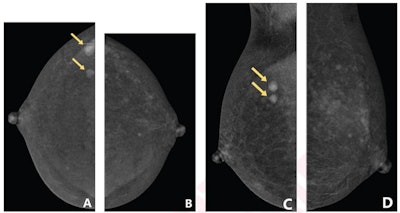

Contrast-enhanced mammography images show that the degree of background parenchymal enhancement (BPE) increases over time after contrast agent injection. (A) Craniocaudal view of the right breast shows mild BPE, whereas subsequently obtained (B) craniocaudal view of the left breast shows moderate BPE. Based on the first criteria reflecting only the first obtained view, the degree of BPE is classified as mild; based on the second criteria reflecting both obtained views, the degree of BPE is classified as moderate. Histopathologic assessment from subsequent biopsy showed that both masses were invasive ductal carcinoma.